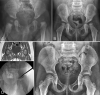

Fig. 5

Left hip dislocation is evident on this AP pelvic radiograph of a 7-month-old girl (A), who subsequently underwent a successful closed reduction. Standing AP radiograph at 3 years of age (B) shows residual hip dysplasia, with right AI = 28° (slightly dysplastic) and left AI = 34° (more clearly dysplastic). MRI revealed a right CAI = 10° and CCE = 25° (reassuring) and left CAI = 19° and CCE = 12° (C). A left Dega acetabuloplasty alone (D) was performed following shared decision-making with the family. Radiographs at the age of 6 (e) demonstrating excellent coverage and a class I Severin outcome